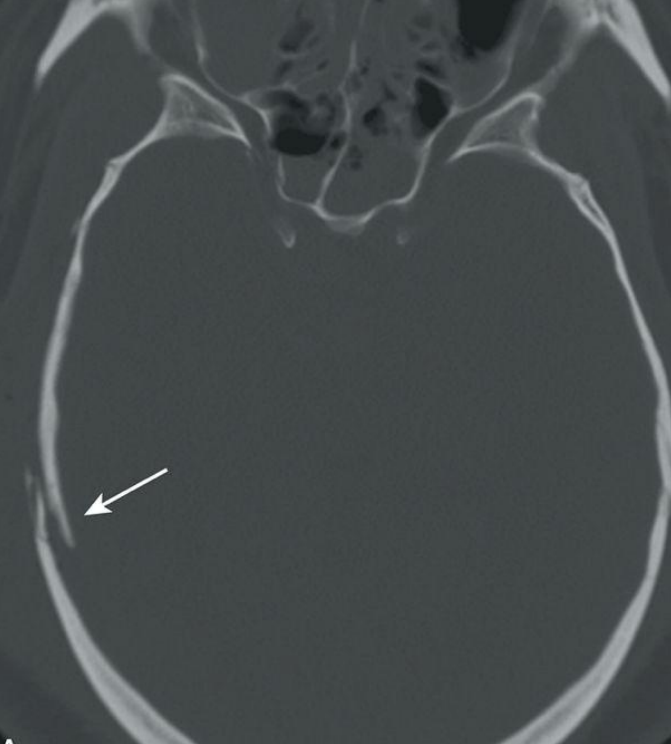

¿Qué fracturas se detectan solo por TC?

A

Fx de base de cráneo

Signos indirectos de fractura de base en TC

Sangre en seno esfenoidal, celdillas mastoideas, neumoencéfalo

Fractura lineal: hallazgos

Línea radiolucente fina; temporal/parietal + frec